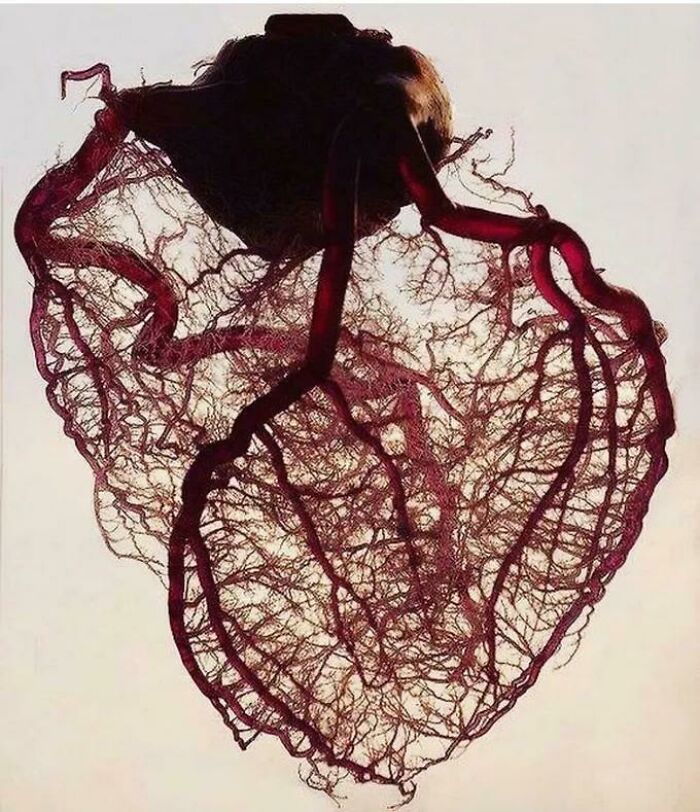

Amazing View Of The Vascularization Of The Heart